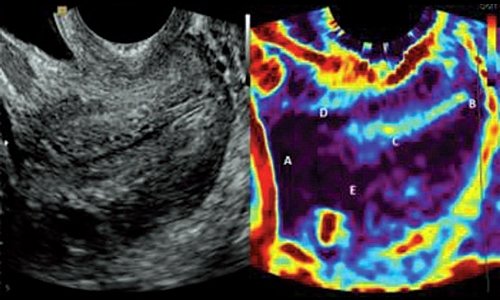

На представленных иллюстрациях, полученных с помощью технологии ЭластоСкан™, показана шейка матки во время беременности. Эхограммы в В-режиме получены с использованием критериев Фонда Медицины Плода для измерения внутреннего зева и длины цервикального канала. При эластографии была использована цветовая карта 2 (со шкалой от фиолетового до красного). Жидкость в мочевом пузыре либо амниотической полости кодируется красным цветом, а кости черепа плода фиолетовым.

Авторами предложена следующая бальная оценка изображений, полученных с помощью ЭластоСкан™: плотным структурам (фиолетовый цвет) присвоено 0 баллов, менее плотным (голубой) 1 балл, зеленый - 2, желтый - 3, красный - 4 баллами. Таким образом, была сформулирована пятибалльная шкала, названная Индексом Цервикальной Эластографии (CEI), а части шейки матки (передняя и задняя губы, внутренний и наружный зевы и цервикальный канал) оценивались в баллах по CEI.

На рис. 1 представлена незрелая шейка матки во время беременности. Консистенция шейки матки одинаковая в области внутреннего и наружного зева, цервикального канала, передней и задней губ. Все части шейки матки, представленные на рис. 1, были оценены в 0 баллов, что можно интерпретировать двояко: вся шейка матки либо плотная, либо мягкая. После проведения около 50 исследований был сделан вывод, что такая картина соответствует ригидной шейке матки без симптомов созревания.

Рис. 1. Шейка матки во время беременности без признаков созревания.